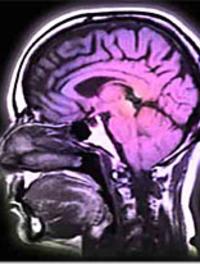

Bien que la tomodensitométrie (TDM) ait été mise au point il y a presque 40 ans et l’imagerie par résonance magnétique (IRM) il y a [...]

L’attitude à adopter face à un traumatisme crânien de faible gravité (défini par une perte de connaissance initiale et/ou une amnésie [...]